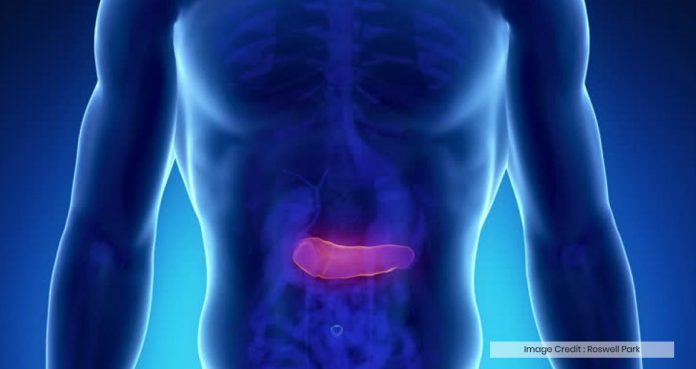

Researchers at the University of Pittsburgh Medical Center (UPMC) have been testing a new treatment method for patients with pancreatic cancer and they found preliminary results quite promising.

Last year, one of the UPMC patients, Darlene Bossola, was diagnosed with pancreatic cancer who made an early decision to fight her cancer by taking part in a clinical trial.

Darlene said, “When you’re diagnosed with stage three, you want something to happen, for the better.”

Darlene used to undergo standard chemotherapy and radiation before enrolling into the trial.

During the trial, Darlene received eight experimental treatments, including a procedure in which doctors inserted a catheter into the pancreas.

UPMC Interventional Radiologist Dr. Paula Novelli said, “We bathe the tumor with chemotherapy directly to the tumor, without having to go through the bloodstream.”

Darlene said she is quite pleased with the results, with little to no side effects.

Bossola said, “I have been feeling good my entire process. I’ve not had any ill effects like nausea. The only effect I’ve had is fatigue.” Doctors will continue to monitor Bossola’s progress.